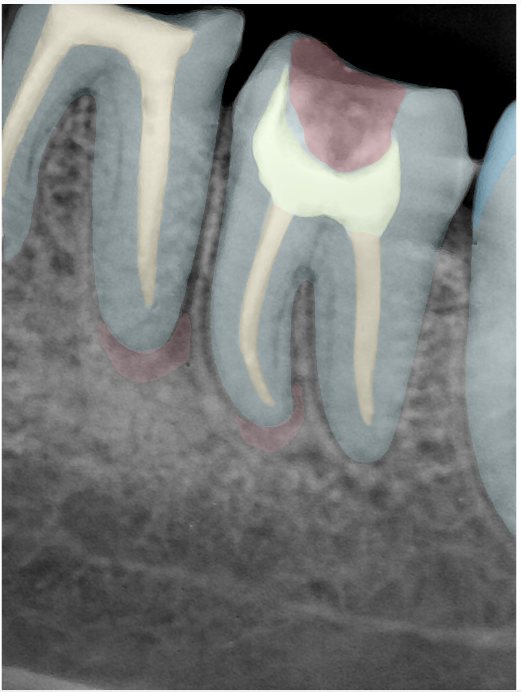

CR/DR 牙齿分割阶段记录

当前进展

- 完成了 CR/DR 牙齿相关分割训练

- 当前结果已经达到阶段预期,但仍有细节问题需要继续处理

相关测试

遇到的问题

- 训练过程中出现过 mask 下移问题

- 部分结果会出现 box 填充异常

- mask 边缘仍然有比较明显的锯齿感

第二版算法问题测试